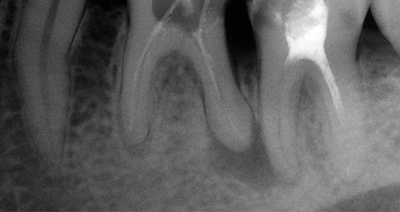

5. Проводит рентгенографическое исследование. Увеличение периодонтальной щели на рентгене свидетельствует о развитии фиброзного периодонтита.

Диагностировать воспаление можно только с помощью рентгеновских снимков, на которых видны фиброзные поражения — аномально широкие полосы между корнем и лункой зуба.

• Фиброзный. Протекает бессимптомно, болей обычно нет, отсутствует реакция на тепло или холод. Развивается как осложнение невылеченного пульпита. Цвет коронки меняется, обычно она имеет глубокую кариозную полость с отмершей пульпой. На рентгенографии видно расширение периодонтальной щели у верхушки корня.